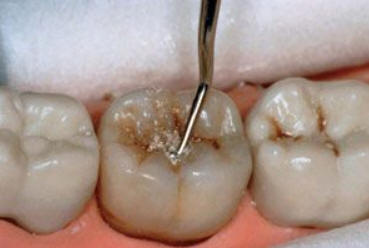

Código 3 (Caries moderada) in vitro. Los códigos 3 in vivo debe ser sellado para evitar el avance del proceso carioso. (MNO)

Código 4 (Caries moderada) in vitro. Los códigos 4 in vivo deben ser tratados en forma operatoria con preservación dental (MOPD), porque presentan dentina infectada.